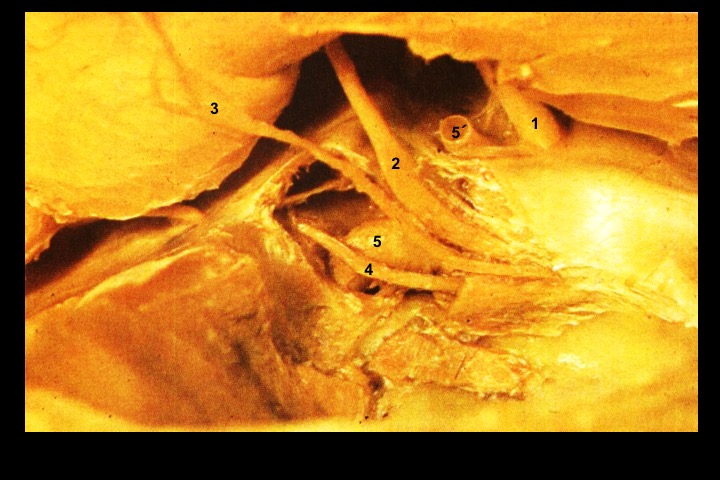

Seio cavernoso_1